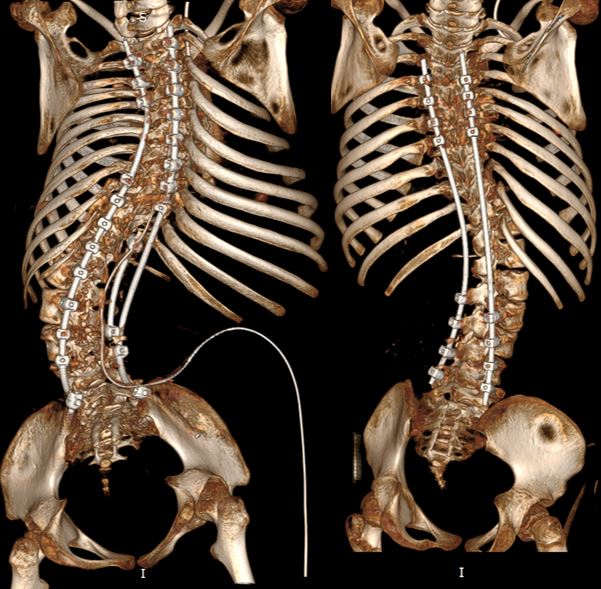

Операция и восстановление

Операции были выполнены ведущими спинальными хирургами России, профессорами Сергеем Геннадьевичем Млявых и Сергеем Олеговичем Рябых, на всех этапах им помогали ведущий детский ортопед, к.м.н. Михаил Анатольевич Петров и нейрохирург Александр Сергеевич Елисеев.

Ранний послеоперационный период у девочек прошёл стабильно и без осложнений.

Сегодня наши пациентки — Махдия и Аиша — возвращаются домой, на Камчатку.

Теперь они могут сидеть без боли и без необходимости постоянного ношения жёстких корсетов, продолжая восстановительное лечение у себя в регионе.

• стабилизировать позвоночник в наиболее гармоничном для сохранения вертикальной позы положении,

• кардинально улучшить качество жизни,

• облегчить уход,

• снизить болевой синдром,

• создать максимально комфортные условия для дальнейшей реабилитации.